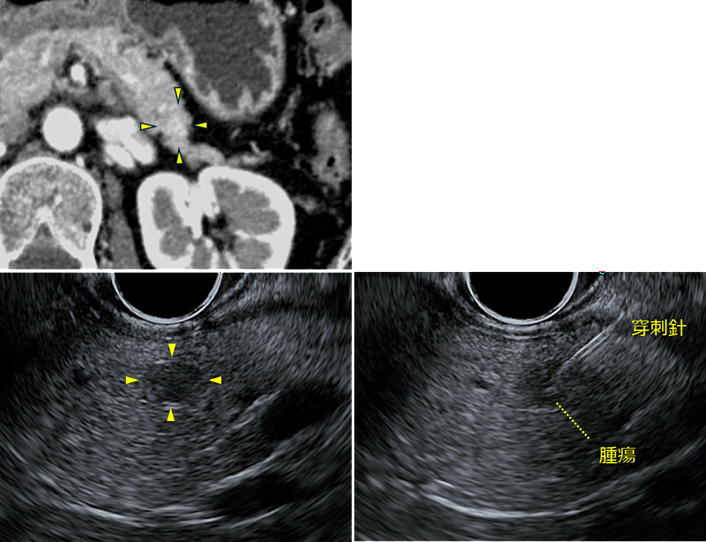

当院で行った造影CT検査では、肝内胆管の拡張の起始部に造影効果を伴う壁肥厚(黄色矢頭)を認めました。

そこでEUS-FNAによる精査を行いました。EUSでは胆管内に低エコー腫瘤を認め(左上)、この病変に対して穿刺を行いました。その結果、腺癌と診断されました。

左:境界明瞭な8mm大の低エコー腫瘤を認めます。

中:FNA針で腫瘍を穿刺します。

右:腫瘍の大きさに合わせてエタノールを注入します。注入後はこのように腫瘍内部が白く変化し、薬剤が腫瘍内に広がったことが確認できます。

超音波内視鏡(Endoscopic Ultrasound:EUS)では、膵頭部に境界明瞭な約8 mmの低エコー腫瘤を認めました。穿刺針で腫瘍を穿刺し、腫瘍内にエタノールを注入しました。エタノール注入後、腫瘍は白く変化し、薬剤が腫瘍内に行き渡ったことが確認されました。